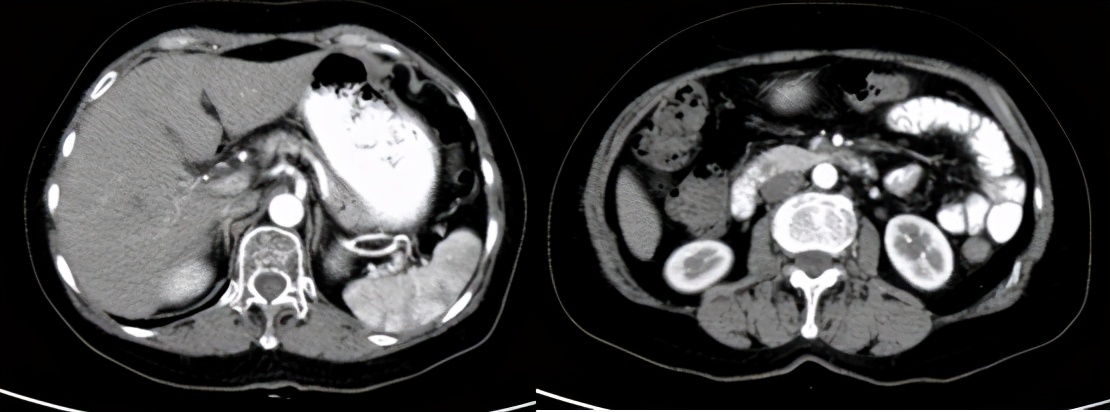

疗效评价:CR,截至2021.4,PFS为12个月,目前仍在随访中。

治疗后随访(2021.4)